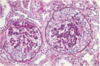

Describe the anatomy of the glomerulus

Note location of the afferent and efferent arterioles, mesangial cells, podocytes, bowman’s capsule, etc.

Explain the terminology used in the histology of glomeruli such as:

Diffuse, Global, Focal, Segmental, Mesangial

Diffuse: invlolves all glomeruli

Global: involves the entire glomerulus

Focal: involves only some of the glomeruli

Segmental: involves only part of each glomerulus

Mesangial: primarily the mesangial region